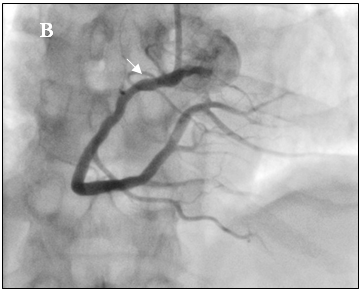

Tại cấp cứu bệnh nhân được chẩn đoán nhồi máu cơ tim cấp vùng hoành giờ thứ 2, block A-V độ 3, có chỉ định chụp mạch vành cấp cứu. Kết quả chụp mạch vành cho thấy hẹp nặng lan tỏa nhiều đoạn ở cả động mạch vành trái (hình 2a) và động mạch vành phải (hình 2b).

Hình 2a: Dấu mũi tên trắng cho thấy nhiều chổ hẹp ở nhánh LCX, OM và LAD

Hình 2b: Hệ mạch vành ưu thế phải, hẹp lan tỏa RCA